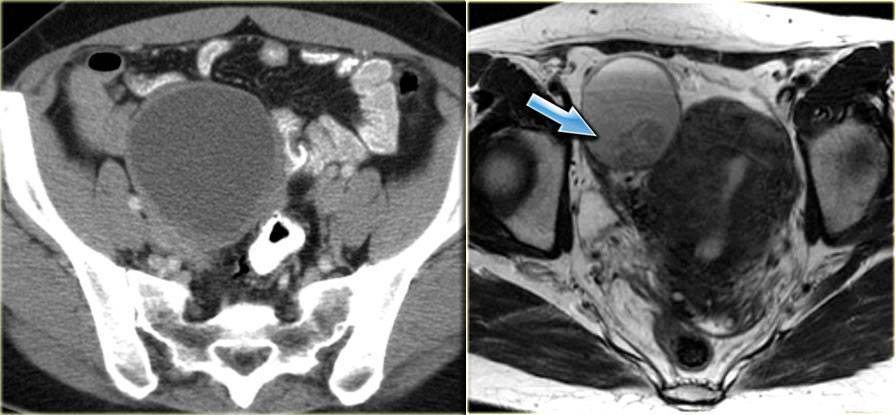

Эндометриоидная киста яичника: МРТ (справа) и КТ (слева). Компьютерная томография используется преимущественно с целью подтверждения кистозного характера образования. МРТ обычно может применяться с целью лучшей визуализации кист, плохо дифференцируемых при УЗИ.

На МРТ геморрагическое содержимое внутри эндометриомы приводит к повышению интенсивности сигнала на Т1 ВИ. На Т1 ВИ с жироподавлением эндометриома остается гиперинтенсивной в отличие от тератом, которые также гиперинтенсивны на Т1 ВИ, но гипоинтенсивны на Т1 FS. Эта последовательность (Т1 FS) всегда должна дополнять МР-исследование, поскольку позволяет обнаружить мелкие очаги, гиперинтенсивные на Т1.